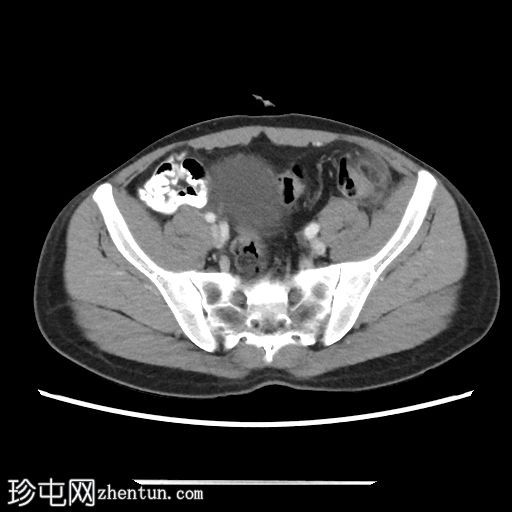

轴位

平扫

乙状结肠-降结肠交界处前缘可见一卵圆形脂肪密度病灶,大小约20 x 7 mm(TR x AP)。病灶周围可见高密度环及脂肪条索影,符合大网膜垂炎的影像学表现。

邻近肠壁可见轻度反应性增厚。

未见腹腔积液或肠系膜淋巴结肿大。